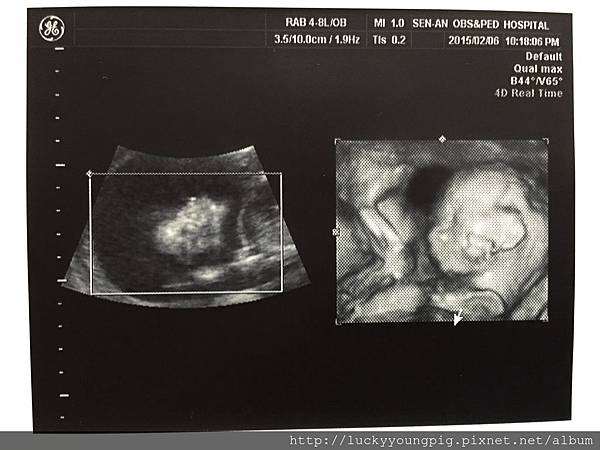

因不是很確定寶貝的姓別 請醫生看一下

醫生說寶貝縮成一團 嗯~等等再看

最後寶貝是男生是女生呢?

醫生說 嗯~應該是女生

醫生又換個角度照 說百分之百是女生

因為這邊有三個點 嗯~大妹與媽咪我真的看不出來啦 +.+